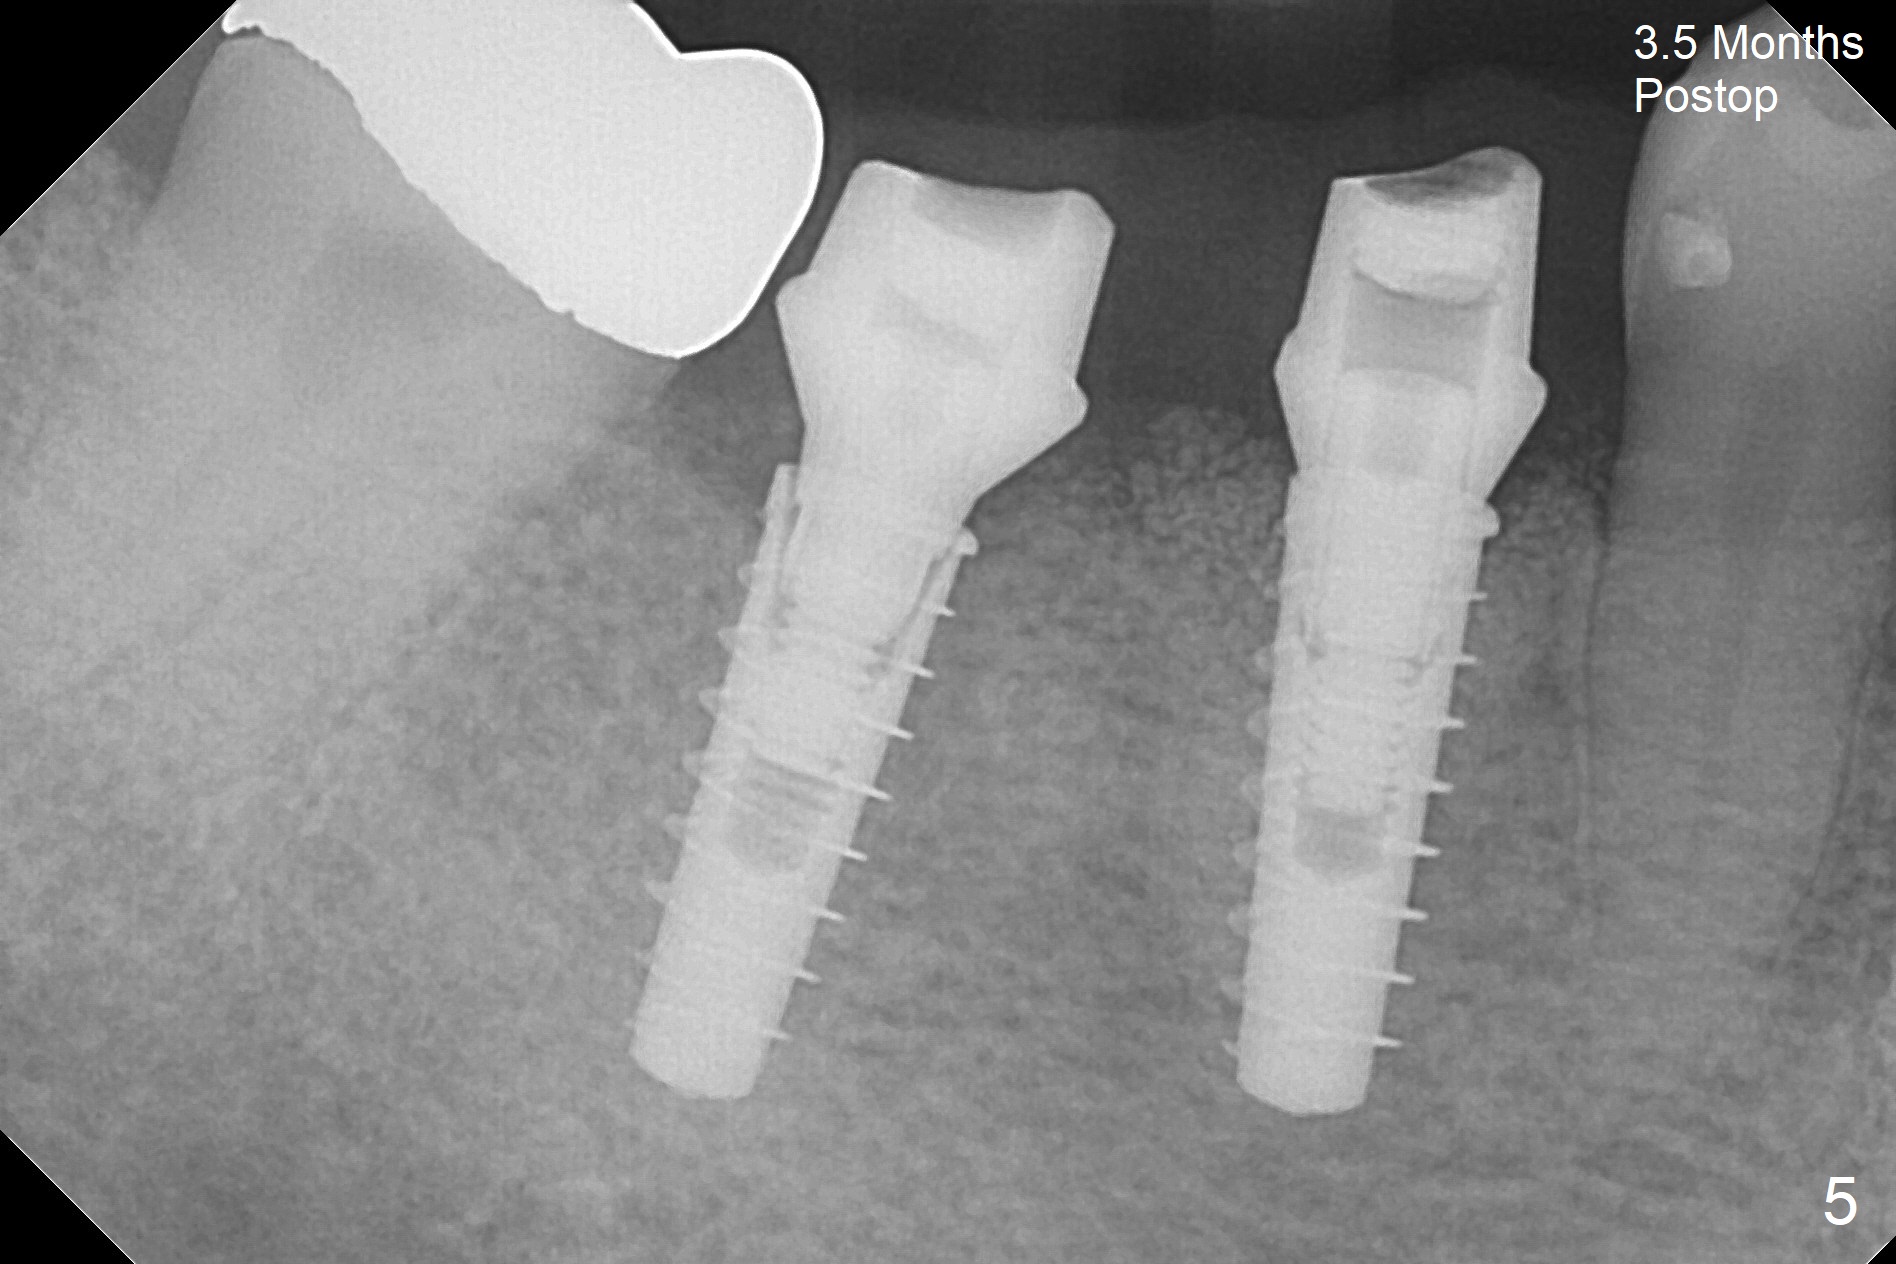

After incision, the ridge at #29 and 30 is found ~ 5 mm wide buccolingually. To place a 4x11 mm IBS implant at #30, the ridge is expanded using BEB technique (bone expansion and bending, Fig.1). It appears that the initial osteotomy at #29 is mesial (Fig.1 yellow dashed line: the distal surface of the root of the tooth #28). After moving the osteotomy distal, the final implant position at #29 (4x11 mm) is within normal limit (Fig.2). The bone at #29 seems to be not so dense that bending (using 1.6 mm drill) is not necessary (using Magic Split and Magic Expanders 3 and 3.8 mm). Later the implant at #30 (4x11 mm) is placed deeper (Fig.3). After placing bone graft around the implants/abutments and suturing, the ridge looks wider with apparent formation of the gingival bands around the abutments (Fig.4 *). Three months and a half postop, bone loss is minimal (Fig.5) and gingival bands forms around the abutments (Fig.6). Fig.7 is taken 1 month post cementation (panoramic X-ray). The patient chews normally 1 year (Fig.8) and nearly 2 years (Fig.9,10) post cementation. The crown at #31 needs recementation 2 years 7 months post #30 cementation; the incomplete seating of the abutment was noted for the first time (Fig.11). Five months later the patient is going to be retired and wants to travel abroad. After approval, the access hole was reopened; articulating paper shows under occlusion of the crown (Fig.12). Since the gap between the abutment and the implant is large, the abutment/crown complex seems to be necessary to be turned (Fig.13 curved arrow). The proximal surfaces of the crown need to be trimmed (straight lines). After turning, the crown sits down with screw tightening; the patient feels pain from the gingival cuff (Fig.14). After turning, the abutment appears to be completely seated (Fig.15). In fact the mesial and distal surfaces of the crown should have clearance from the neighboring teeth (Fig.14) so that pick-up impression is able to hold the crown/abutment complex securely (Fig.16: *). The crown is separated from the abutment after crown repair. They are seated together (loose connection) using the crown as a guide to seat the abutment. BW is taken without the crown. It appears that the abutment remains seated completely (Fig.17). The apical space is equal between #29 and 30 (Fig.17, as compared to Fig.5).